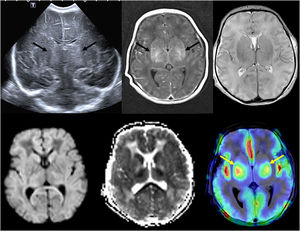

A)Ecografía transfontanelar realizada en el primer día de vida en neonato a término con hipoxia-isquemia grave que demuestra lesión bilateral de sustancia gris central (flechas). B)RM craneal realizada a los 4días de edad que demuestra lesión bilateral de sustancia gris central en las secuencias T1, T2, con restricción en difusión, con evidencia de perfusión elevada en ASL (flechas), lo cual se ha correlacionado con mal pronóstico.

Avances en resonancia magnética (RM)En los últimos años la RM ha experimentado importantes innovaciones, sobre todo en la reducción de los tiempos de exploración. La RM rápida es un método que limita los tiempos de exploración lo suficiente como para evitar la sedación, siendo utilizada habitualmente para el cerebro, pero también en el dolor abdominal agudo y las infecciones musculoesqueléticas. El método Dixon de supresión de grasa es más uniforme y proporciona imágenes con y sin supresión de grasa en una sola adquisición. La imagen por tensor de difusión (diffusion tensor imaging [DTI]) permite cuantificar la difusión anisotrópica en diversas direcciones, con ulterior construcción de mapas de anisotropía representando la dirección de los tractos o tractografía, la cual puede representar cambios microestructurales en el tejido cerebral, tanto los fisiológicos asociados a la mielinización y desarrollo cerebral normal, como en diversos trastornos o en cambios posteriores al tratamiento. Esta técnica ayuda al neurocirujano a reducir la morbilidad al resecar la mayor cantidad de tumor posible, preservando los tractos más importantes de sustancia blanca, como las vías corticoespinales, responsables de la función motora, o el fascículo arqueado, responsable del lenguaje. La perfusión ASL (arterial spin labeling) es un método de perfusión que no requiere gadolinio, pues utiliza el agua de la sangre como marcador endógeno, con la ventaja de su carácter no invasivo. Puede mostrar cambios en la perfusión cerebral en diversas anomalías como ictus, convulsiones, migrañas complicadas, o neoplasias cerebrales (figura 2). La RM espectroscopia (RMs) proporciona información metabólica complementaria a las imágenes neuroanatómicas y es especialmente útil en las neoplasias cerebrales, contribuyendo a determinar el grado de malignidad, así como a valorar la respuesta al tratamiento. La RM funcional (RMf) utiliza los cambios dependientes del nivel de oxigenación sanguínea, siendo su principal utilidad la planificación prequirúrgica previa a la resección de lesiones como tumores cerebrales, malformaciones vasculares o focos epileptógenos cercanos a la corteza elocuente. Las áreas elocuentes del cerebro que se estudian con mayor frecuencia incluyen las áreas motoras, del lenguaje y visuales, mediante diversos paradigmas basados en tareas. La técnica SWI (susceptibility weighted image) es una técnica de eco de gradiente 3D, de alta resolución espacial, que acentúa las propiedades magnéticas de productos sanguíneos, calcificaciones y hierro, siendo sensible en la detección de microhemorragias y en diferenciarlas de las calcificaciones, o en demostrar la vascularización anómala en los tumores de alto grado3.